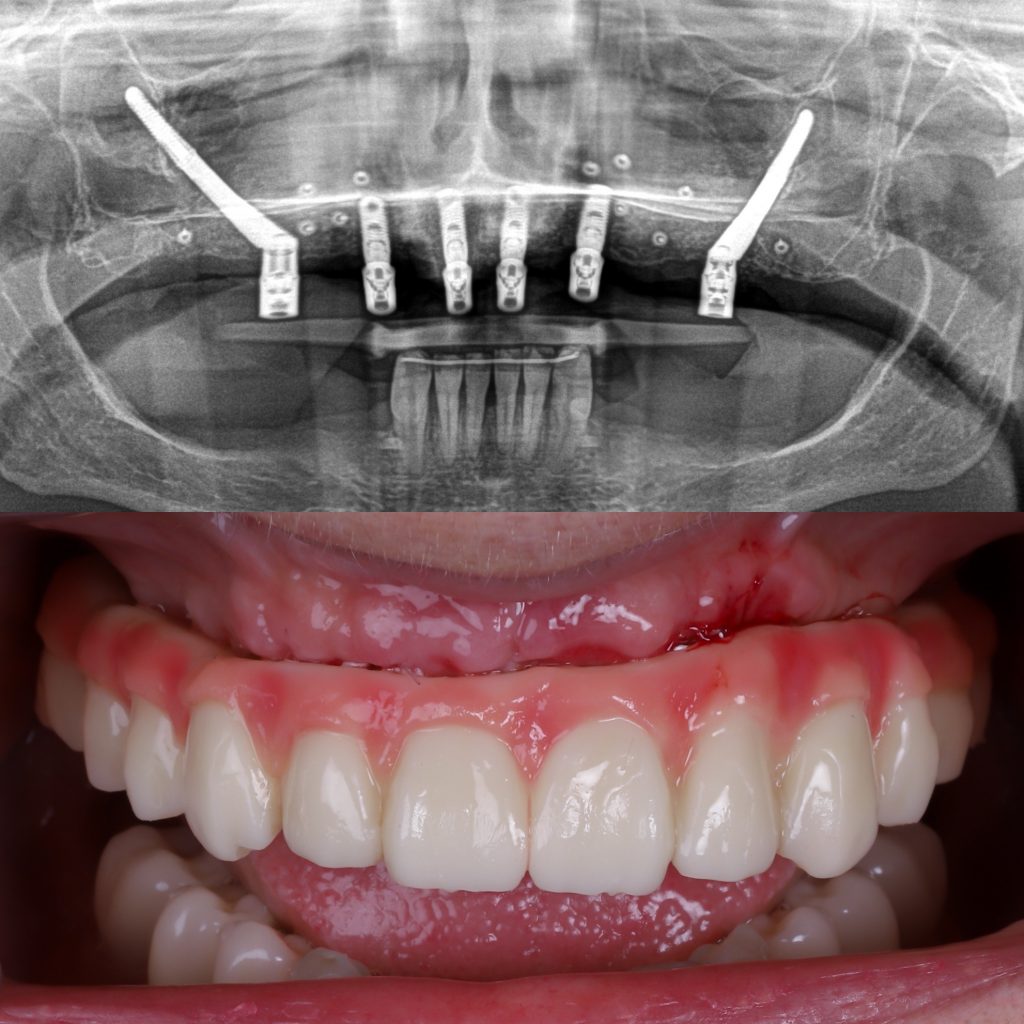

El número de implantes cigomáticos necesarios suele variar entre 1 y 4 por arcada y depende principalmente de la calidad del hueso maxilar y la calidad del hueso cigomático (pómulo). Cuando el hueso del maxilar no es suficiente, utilizamos el hueso cigomático (el pómulo) como punto de anclaje.

Si la pérdida ósea solo afecta a una parte del maxilar, es posible colocar un solo implante cigomático en la zona con peor hueso y completar el resto de la sujeción con implantes tradicionales, que es una cirugía más sencilla y más económica.

Sin embargo, cuando no existe buen hueso maxilar en ninguna zona, o incluso cuando el punto de apoyo en el pómulo no ofrece la estabilidad ideal, pueden necesitarse hasta 4 implantes cigomáticos para conseguir una fijación segura y permitir una rehabilitación fija inmediata.

Por eso es fundamental realizar un estudio personalizado con TAC 3D, que permite definir la combinación más segura, estable y adecuada para cada paciente.

Permiten colocar dientes fijos en 24 horas mediante la técnica carga inmediata.

Antes y después